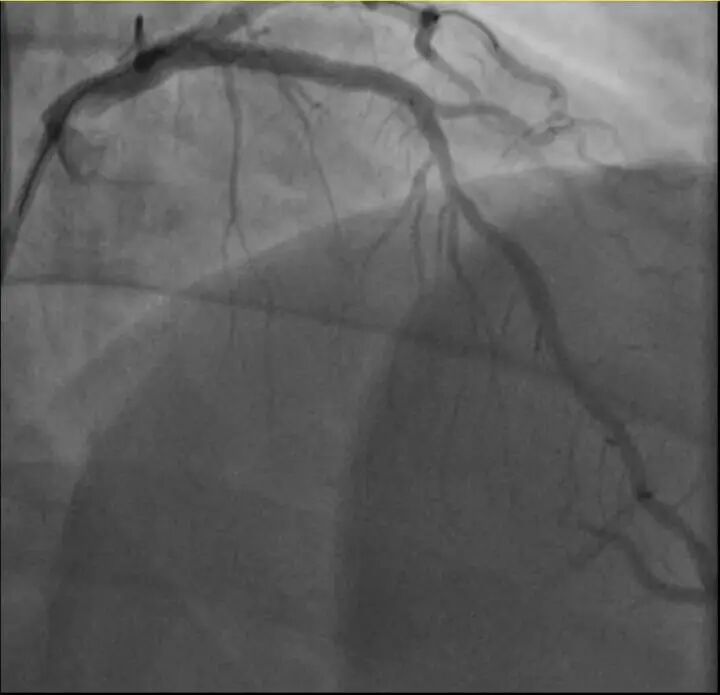

他的血糖一直偏高,服药后控制不佳,但年轻的钱先生并没有太上心。周末,他和孩子爬了一座山,隔天,钱先生就因突发胸骨中段压榨性疼痛被送到了急诊,最后被证实也是心梗——心脏三支主要血管之一回旋支远段次全闭塞。

浙江医院心血管内科翁莹政医师介绍,这位患者来院时血糖12.79mmol/L(正常空腹值应该在3.9~6.1mmol/L),甘油三酯也超标。“三高”(高血压、高血脂、高血糖)是导致动脉粥样硬化(包括心脏的冠状动脉)的主要危险因素,在冠状动脉粥样硬化早期,血管狭窄可能并不严重,仅当血管狭窄到一定程度时,在运动、情绪激动等情况下,心肌耗氧量增加,就可能造成心梗等急性心肌缺血事件。所幸经过汤益民团队的及时介入治疗,钱先生也转危为安。